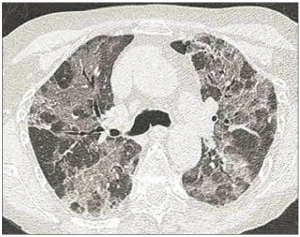

Mme F., 76 ans, désaturation et fébricule : dans un contexte d’immunosuppression…

Présentation du cas Une patiente de 76 ans se présente aux urgences pour une fébricule à 38,1 °C avec frissons depuis 2 jours. Elle a pour antécédents une ostéoporose sous…